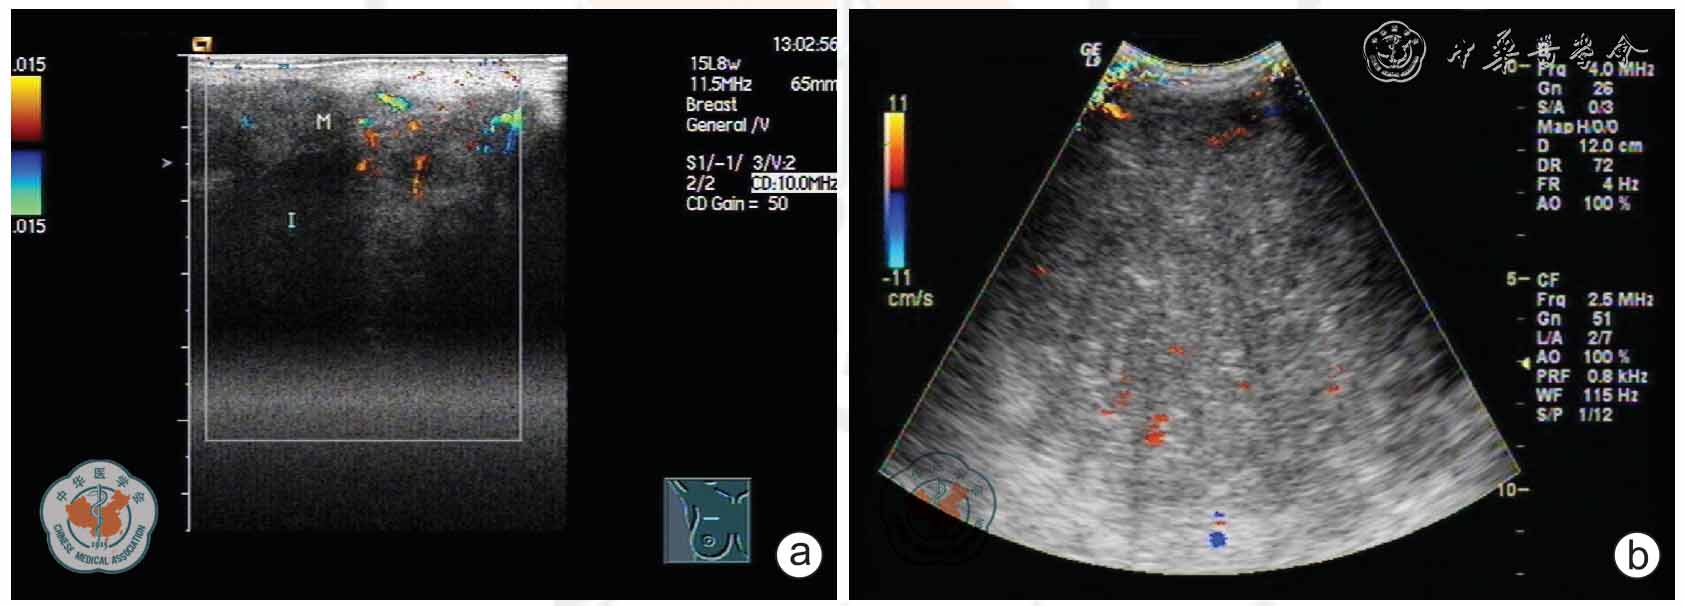

Giant phyllodes tumor in both breasts: one case report and literature review